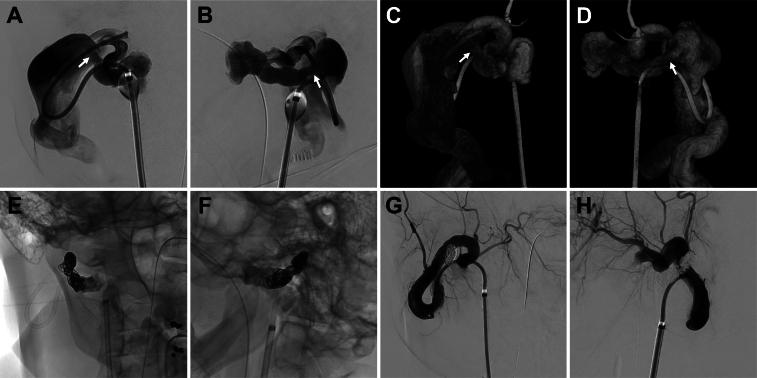

A 45-year-old woman with no history of trauma had been diagnosed with a congenital cervical external carotid AVF 10 years earlier. At that time, only a pulsatile neck mass in the right neck had been observed, and she had been managed conservatively. Over the next 10 years, the right neck mass had enlarged, and she started experiencing unbearable headaches and neck pain when she turned her head. Angiography images showed that the outflow veins, including the external and internal jugular veins, were more dilated and tortuous than they had been 10 years earlier. During neck rotation, the internal jugular vein constricted, causing intracranial venous reflux. Complete occlusion of the shunt was achieved with coils and n-butyl-2-cyanoacrylate. Immediately after surgery, the pulsation in the right neck, the unbearable headaches, and neck pain on neck rotation resolved.

Even in adults with congenital cervical external carotid AVFs that have been managed as simple neck masses, progressive dilatation and tortuosity of the outflow veins can, over time, lead to venous reflux during neck rotation and can cause unbearable headaches and neck pain. https://thejns.org/doi/10.3171/CASE24407.